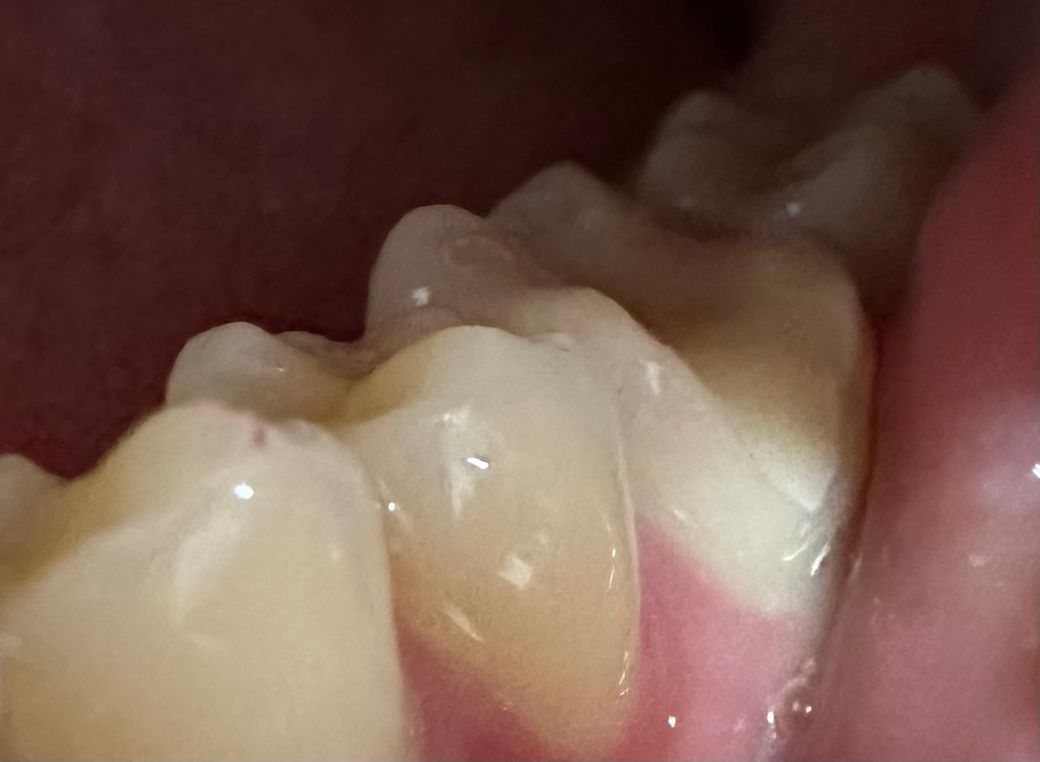

• 2번 째 사진

엑스레이로는 옆면 충치라 잘 보이지 않는다며 사진을 찍어 치아를 직접 보여주셨고 겉보기에는 작아 보이지만 파내 보면 클 수도 있다고 하셔서 일단 조금만 파보기로 했어요

그런데 실제로 파보니 생각보다 충치가 깊다고 하셨어요

다만 어제 넣어두었던 임시 재료를 치위생사분이 제거하는 과정에서 치아가 많이 갈린 것 같아 시린 느낌이 들었고 남아 있는 치아가 많지 않아 인레이를 할 경우 나중에 부러질 위험이 크다며 크라운 치료를 권유받았어요